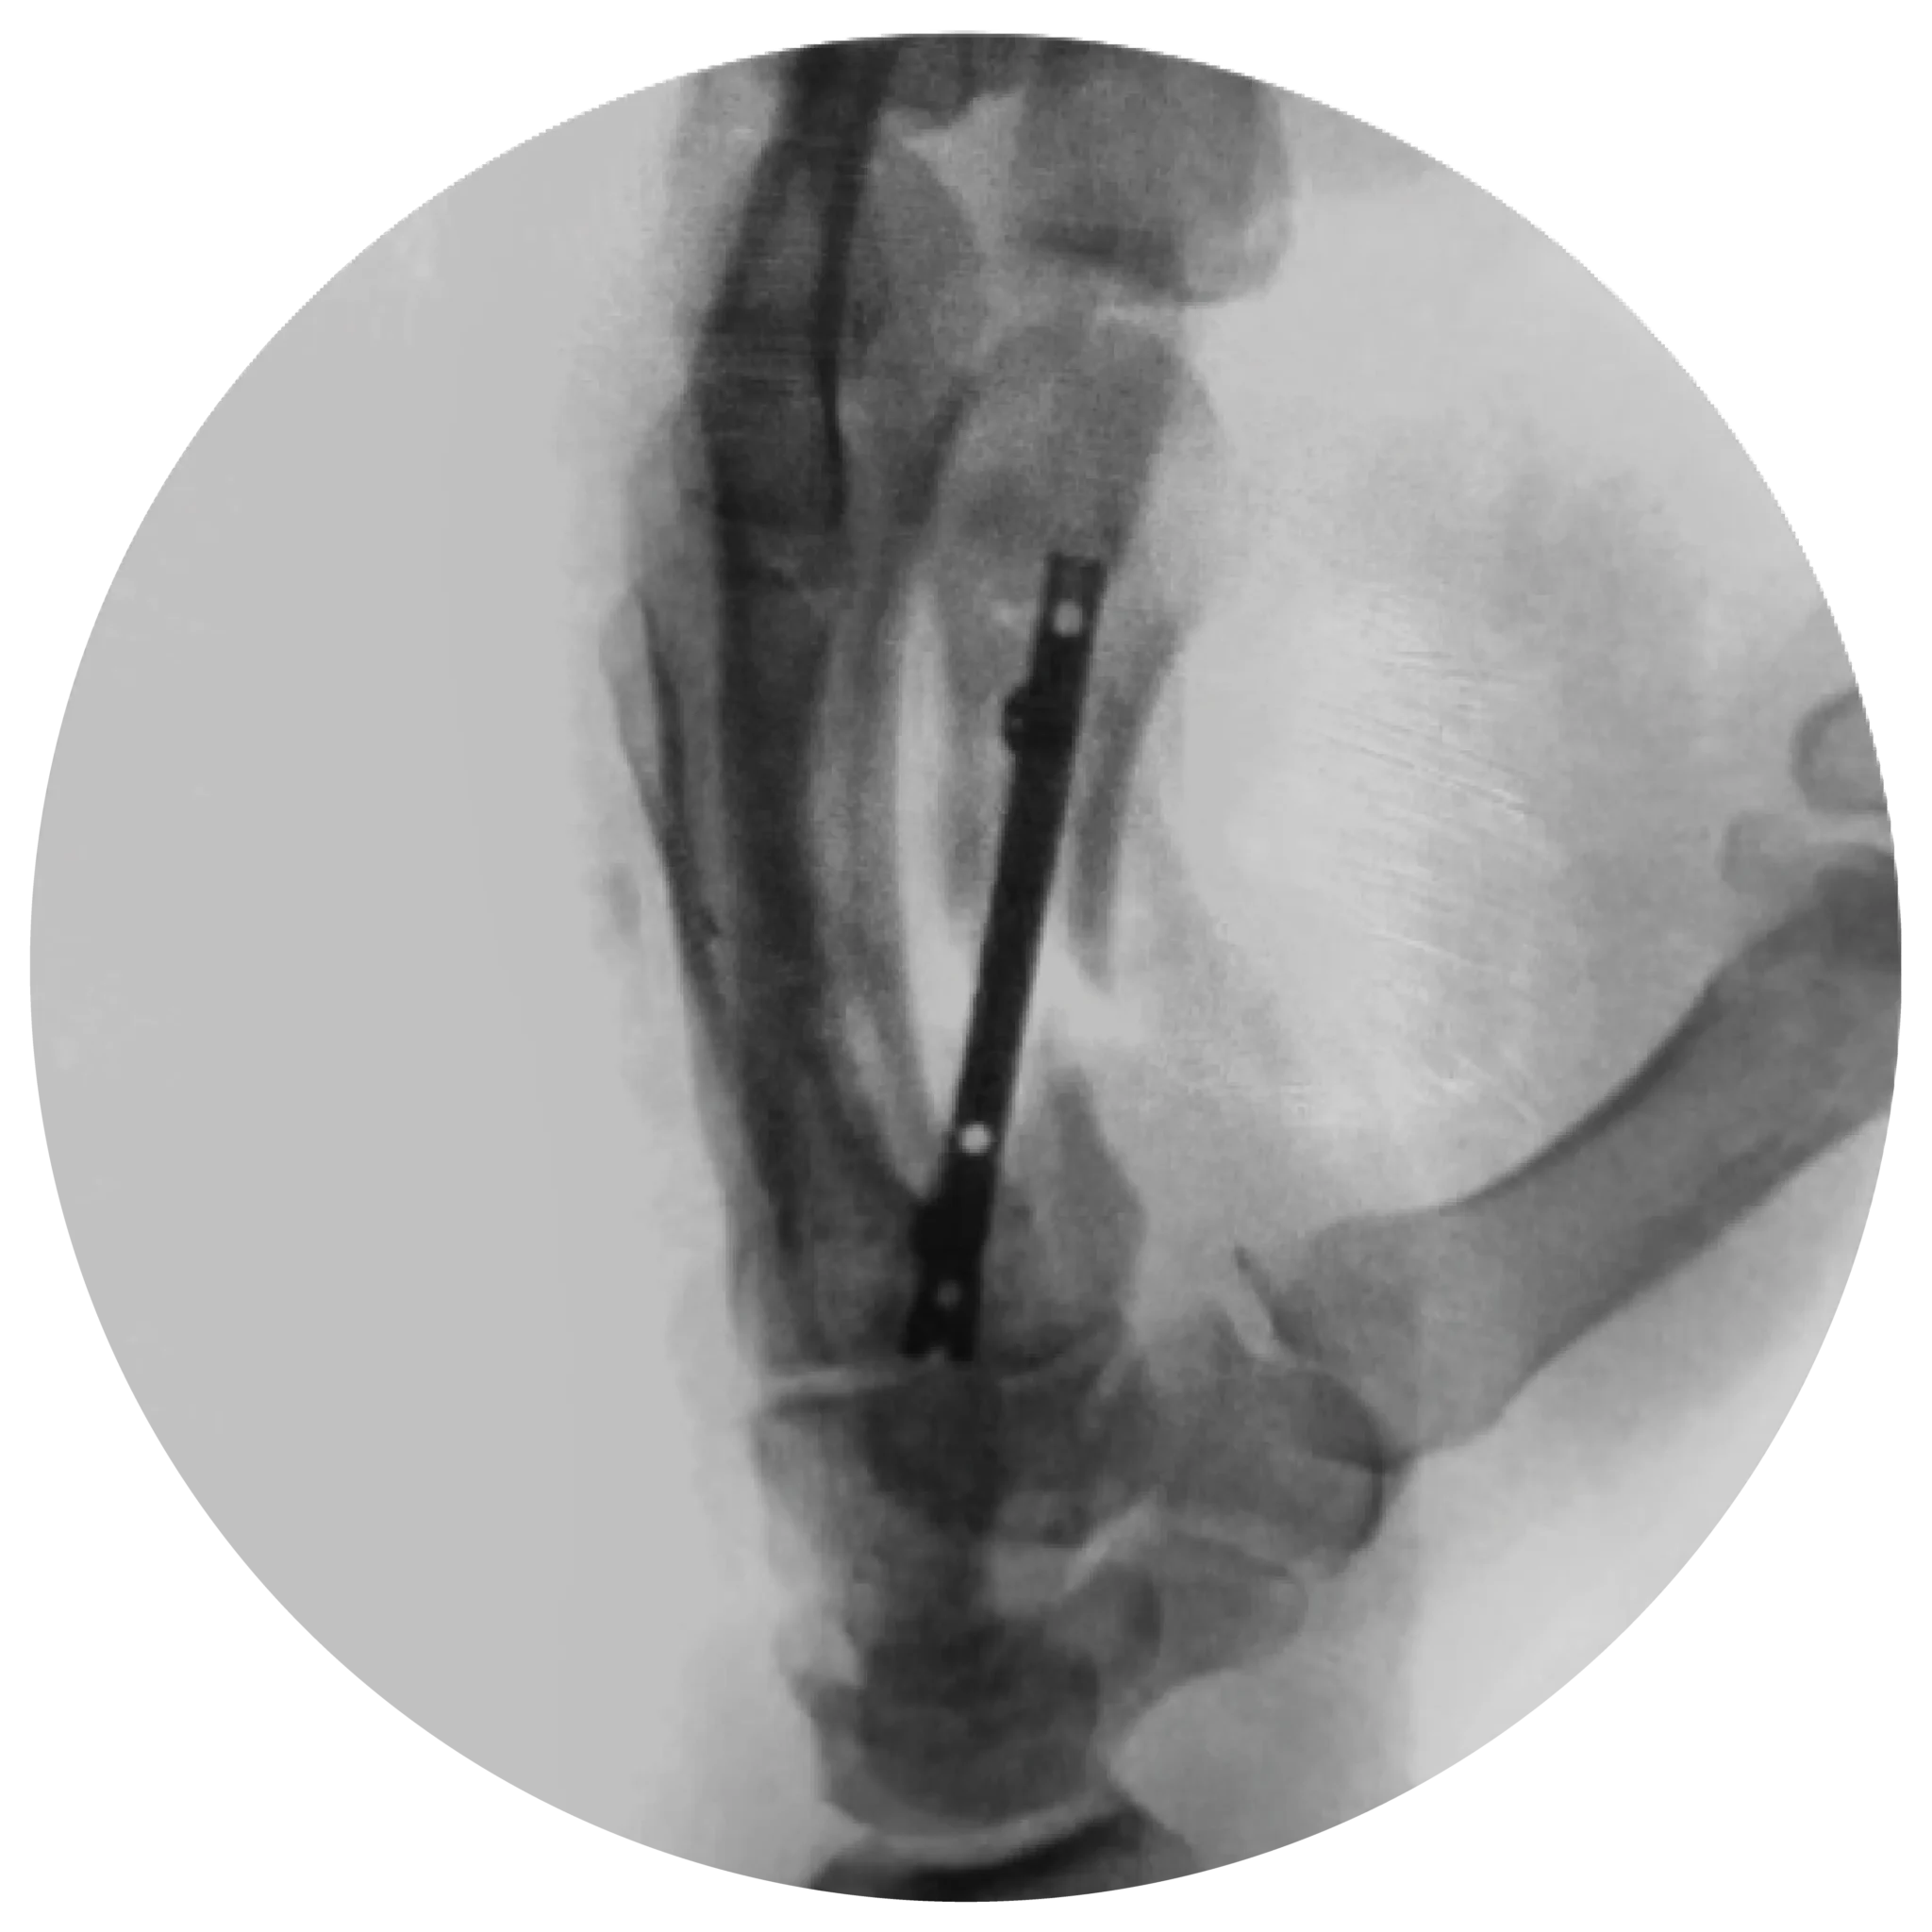

Ideal for Complex Fractures: Perfect for scenarios with bone comminution or loss, where maintaining length and preventing rotation are critical.

Enhanced Stability: Locking compression screws compress the nail to the endosteal surface.